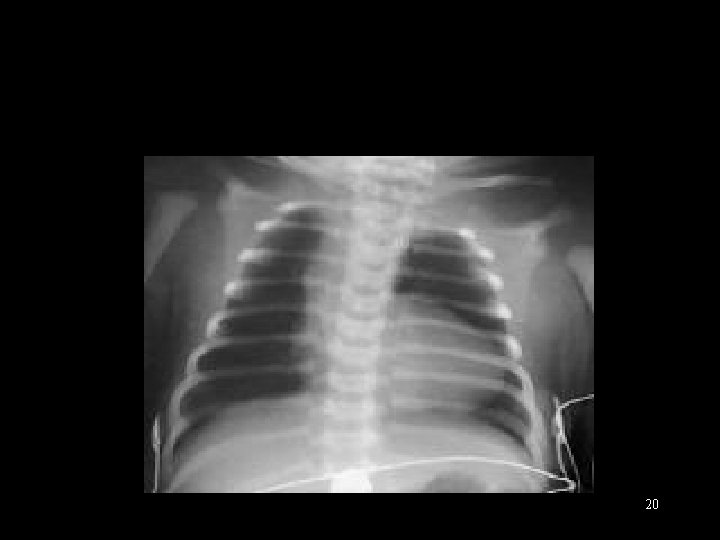

Right Sided Obstructive Lesions. Blue, but comfortable § § Cyanosis No respiratory distress Normal pulses and perfusion Single second heart sound (no closing sound from abnormal pulm valve) § Murmur § Moderate to marked hypoxemia § CXR: normal to large sized heart, decreased PBF 19

20

Tetrology of Fallot 21